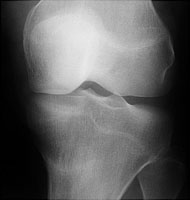

- Click on the image for a larger versionAAP radiograph of the knee. There is a band of sclerosis through the proximal tibia. This represents a stress fracture.

Stress fractures are either the result of abnormal stress placed on normal bone (fatigue fracture) or normal stress placed on abnormal bone (insufficiency fracture). The latter are seen in osteomalacia, rheumatoid arthritis, renal osteodystrophy, osteogenesis imperfecta, and Paget's disease. The former are classically seen in military recruits (march fracture) or weekend athletes, occurring in the tibia, calcaneus, or sacrum.